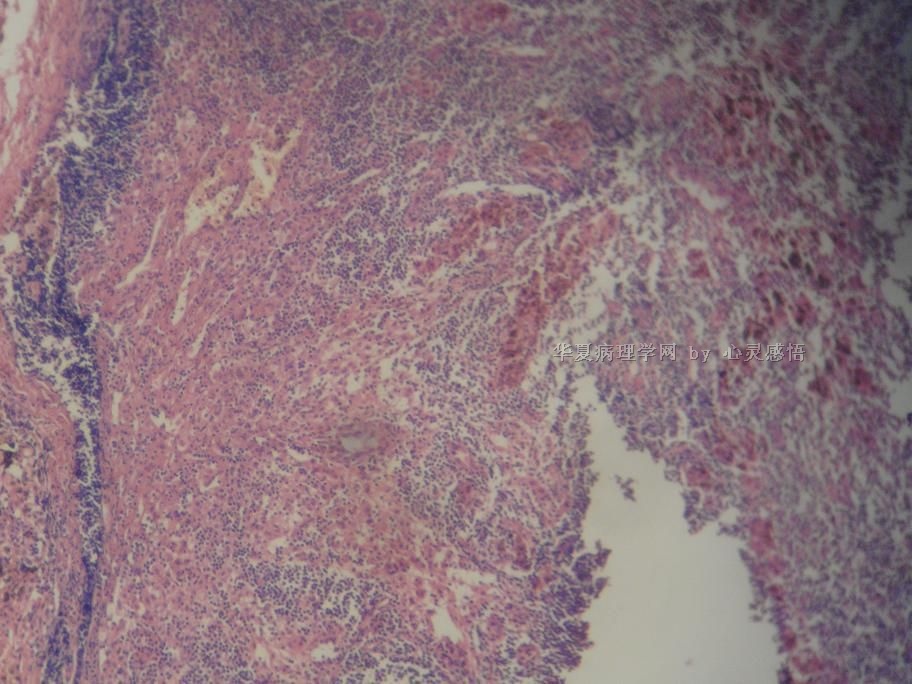

• 食道癌,淋巴结有没有转移,谢谢。图4

图4

1-6图是鳞癌。7-22图片无癌。

淋巴结没有转移

没有转移,食道旁的淋巴结和肺旁的淋巴结相似,含有吞噬细胞。